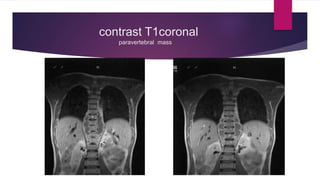

contrast T1coronal

paravertebral mass

contrast T1 coronal

 A well outlined Isointense on T1, Hyperintense on T2 , moderately

enhanced mass lesion on contrast in extramedullary intradural

compartment from D10- D12 on left side compressing and deviating

theca to right

 Another long multi septate fusiform rim enhanced hypointense mass lesion in

anterior paravertebral region extending from T7 –L1 level